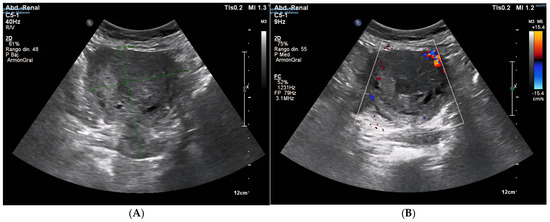

2. Case Presentation